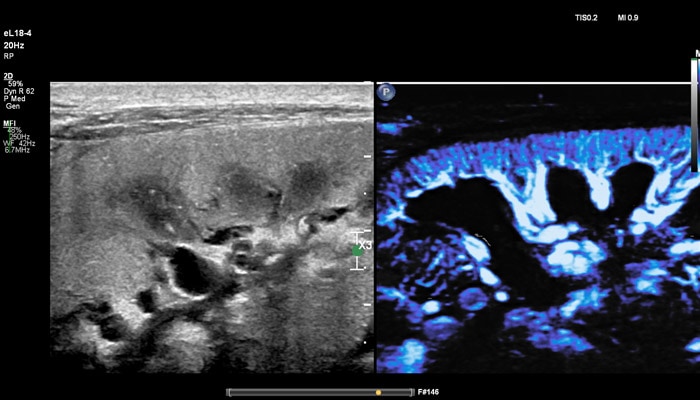

Линейный матричный датчик eL18-4 используется клиницистами Европы как современное решение для визуализации молочных желез, которое повышает надежность диагностики с помощью таких мощных инструментов, как превосходная визуализация в B-режиме, компрессионная эластография, эластография сдвиговой волной и высокочувствительная визуализация кровотока (MicroFlow Imaging). Кроме того, панорамный режим полезен для оценки распространенности заболевания, выявления большого количества фиброзных изменений и определения расстояния между двумя очагами. Всякий раз, при исследовании молочной железы, превосходное качество изображения и эластография необходимы, чтобы поставить точный диагноз с первого раза и помочь в лечении пациентов.

Визуализация кровотока

Philips Microflow Imaging

Линейный матричный датчик eL18-4 поддерживает режим высокочувствительной визуализации кровотока (Philips MicroFlow Imaging), новый запатентованный метод, который обеспечивает инновационный подход к оценке сосудистого русла. Визуализация MicroFlow преодолевает многие барьеры, связанные с традиционными методами обнаружения кровотока в малых сосудах, обеспечивая высокое разрешение при минимальных артефактах.

Метод MicroFlow Imaging поддерживает высокую частоту кадров и качество изображения, применяет инновационные методы сокращения артефактов. Варианты вычитания 2D-изображений, смешивания и параллельного отображения обеспечивают превосходную визуализацию в различных клинических случаях.